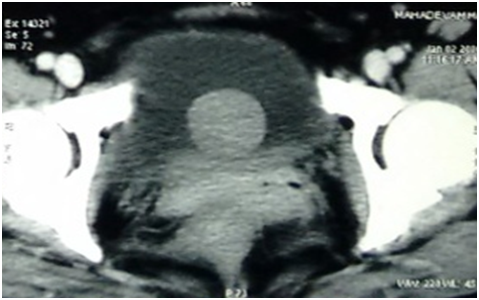

A 53year old lady presented with urgency and frequency for 3months, with two episodes of painless total gross hematuria. She developed acute urinary retention and was catheterized elsewhere and referred to our institute. She had no urological or spine surgeries, no known comorbidities or prior episodes of hematuria. Clinical examination was unremarkable. Ultrasound (US) showed a heterogeneously hypoechoic lesion of 4 x 3 x 4cm in bladder base (Figure 1). Contrast enhanced computed tomogram (CECT) showed a 5 x4 x 4cm well circumscribed hypodense lesion arising from trigone, without hydroureteronephrosis (Figure 2). At cystoscopy, a mucosal bulge measuring around 5 x 5 cm was seen in the right lateral wall extending upto bladder neck and a cecoureterocele was suspected (Figure 3). Transurethral resection (TUR) was done and it showed fragments of tumor tissue composed of spindle cells arranged in sheets and interlacing fascicles, without mitosis or necrosis, suggestive of leiomyoma bladder (Figure 4). Immunohistochemistry showed smooth muscle antigen (SMA) and desmin positivity (Figure 5). Repeat TUR and complete enuceation of the lesion was done. At 6 months of follow up patient is doing well without recurrence or hematuria.

Figure 2 Contrast enhanced computed tomogram (CECT) showed a 5 x4 x 4 cm well circumscribed hypodense lesion arising from trigone, without hydroureteronephrosis.